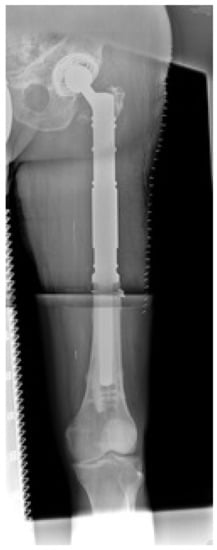

En-Bloc Resection of Metastases of the Proximal Femur and Reconstruction by Modular Arthroplasty is Not Only Justified in Patients with a Curative Treatment Option—An Observational Study of a Consecutive Series of 45 Patients

1. Introduction

2.3. Surgical Technique and Postoperative Care

3.3. Radiographic Evaluation